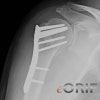

외과목(surgical neck) 부위에서 전위가 된 2조각 골절, 전위가 있는 3, 4조각 골절은 수술을 고려합니다.

3-part ORIF